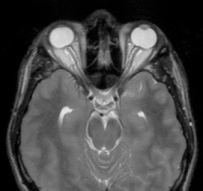

- ses conséquences ophtalmologiques (ci-contre)

- dilatation de la gaine du nerf optique,

- bombement papillaire

- aplatissement des globes